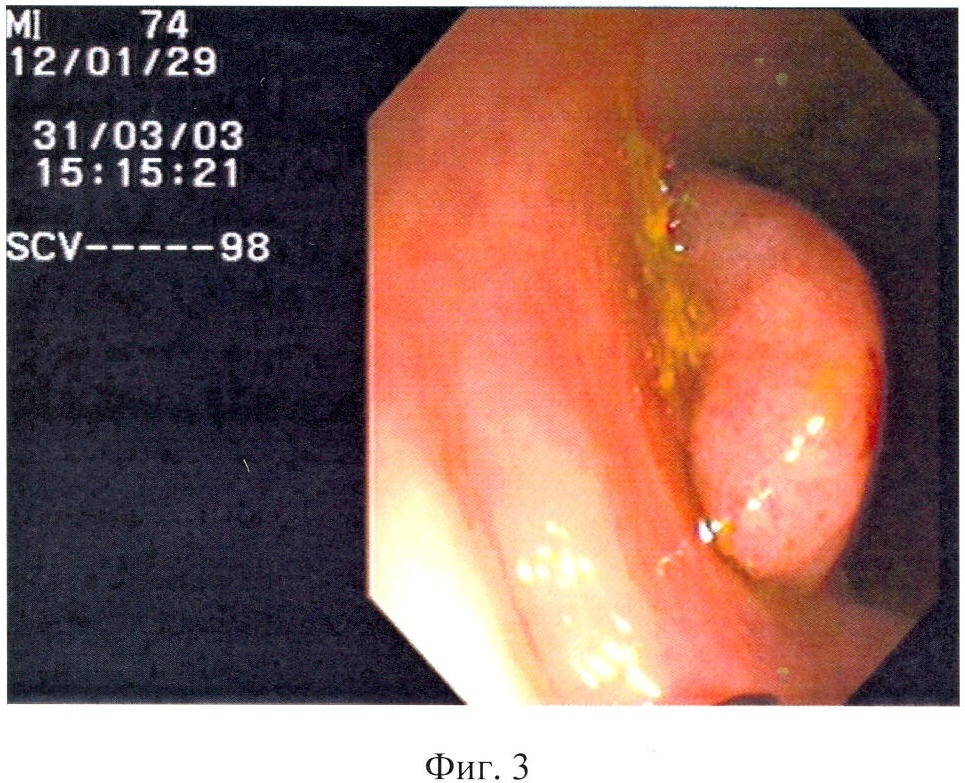

В верхней трети сигмовидной кишки расположен неправильной формы полип на узком основании, размером 0,9×0,6 см, розового цвета, не реагирует на инструментальную пальпацию (фиг.3).

Суммарный критерий = Группа по размеру + Энд. Тип + Цвет + Форма + Поверхность + Ранимость = 81+72+17+93+12+7=282 балла

Таким образом, суммарный балльный критерий равен 282 баллов, что означает наличие облигатного предрака и высокую вероятность рака в полипе.

31.03.2003 года выполнена полипэктомия методом петлевой электроэксцизии.

Гистологическое исследование 14130-14132: тубулярно-ворсинчатая аденома сигмовидной кишки с тяжелой дисплазией эпителия и поверхностными микрофокусами cancer in situ (фиг.4).